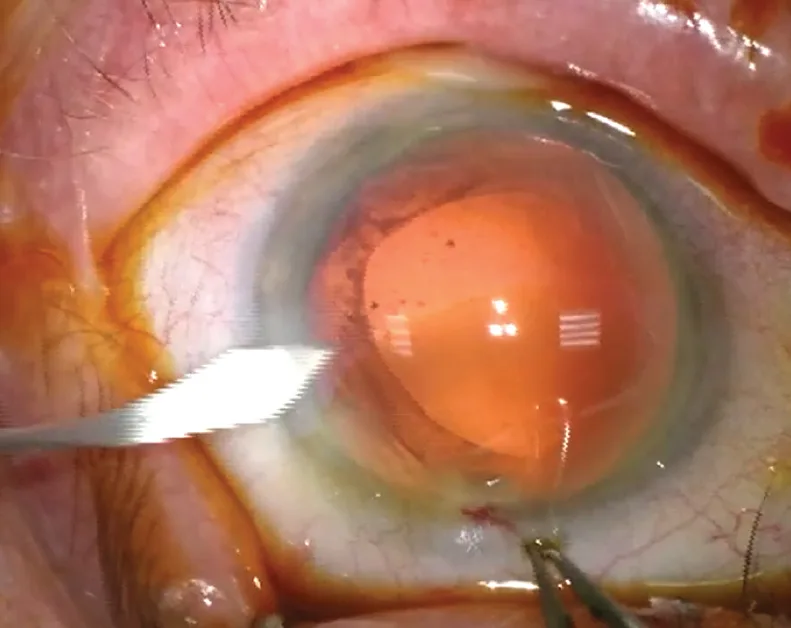

Figure 3.1 S’ouvre dans une nouvelle fenêtre . Incision sclérale : phase de tunnélisation au couteau de Crescent.

Figure 3.1 . Incision sclérale : phase de tunnélisation au couteau de Crescent.

Aujourd’hui, ces dernières sont indiquées uniquement en cas d’altérations importantes de la cornée périphérique, soit primitives, comme les fontes stromales séquellaires périphériques, soit post-chirurgicales comme les kératoplasties transfixiantes de grand diamètre, les kératotomies radiaires serrées ou encore les capots de laser in situ keratomileusis (LASIK) décentrés. La largeur des incisions a progressivement diminué, pour s’établir actuellement entre 1,7 mm et 2,2 mm en chirurgie coaxiale (vidéo 9, cas 3 et 4), et entre 1 mm et 1,6 mm en chirurgie bimanuelle (vidéo 9 , cas 2 ). Ainsi les objectifs de sécurité, d’innocuité et de résultat réfractif ont progressivement façonné les incisions cornéennes d’aujourd’hui.